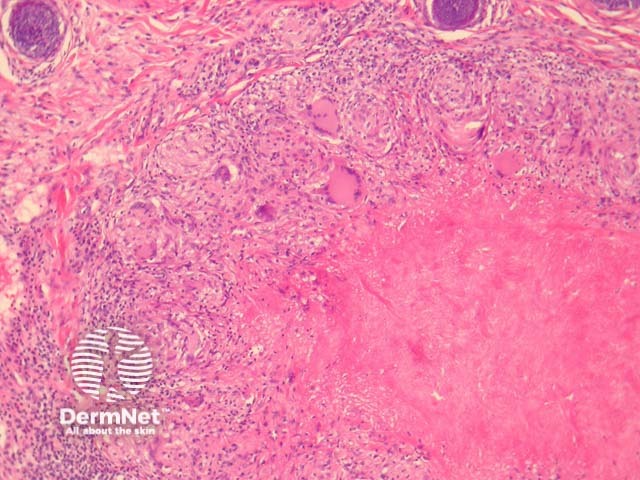

In LMDF, sections show round granulomas with central caseating necrosis. The granulomas may appear sarcoidal or tuberculoid. The granulomas typically arise adjacent to adnexal structures. A chronic infiltrate often accompanies the granulomas. See figures 1-4.